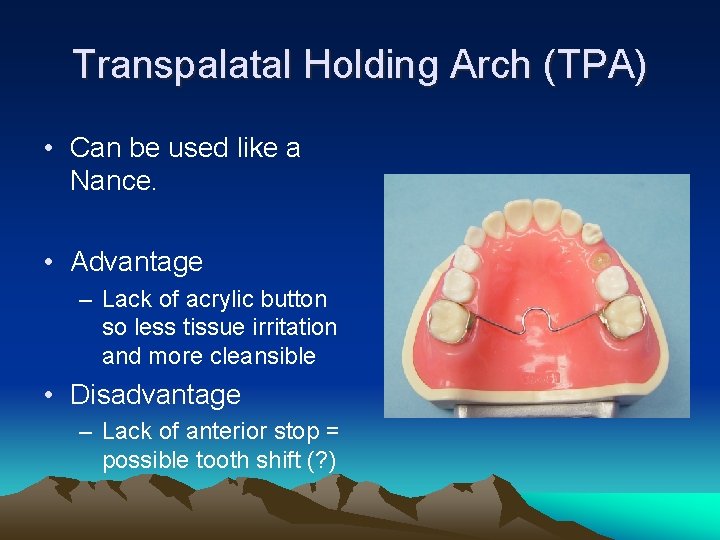

Transpalatal Holding Arch (TPA) • Can be used like a Nance. • Advantage – Lack of acrylic button so less tissue irritation and more cleansible • Disadvantage – Lack of anterior stop = possible tooth shift (? )